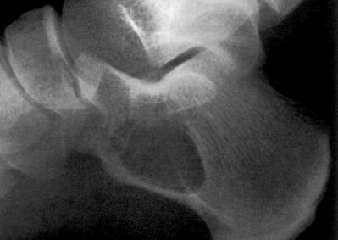

股骨头骨骺缺血性坏死:骨骺变小、碎裂变形,颈短粗,头向外移,内侧间隙增宽。

成人股骨头缺血性坏死:股骨头变形,增骨质生硬化囊变并存;左侧间隙变窄,右侧间隙正常。关节间隙变窄,退行性骨关节病,股骨头呈磨菇头状变形